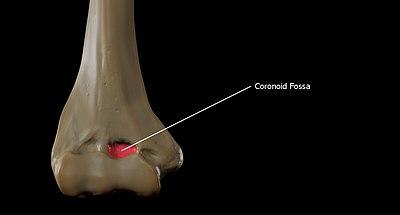

Fossae

Above the front part of the trochlea is a small depression, the coronoid fossa, which receives the coronoid process of the ulna during flexion of the forearm.

The coronoid fossa is the medial hollow part on the anterior surface of the distal humerus. The coronoid fossa is smaller than the olecranon fossa and receives the coronoid process of the ulna during maximum flexion of the elbow.

Coronoid Fossa of the Humerus